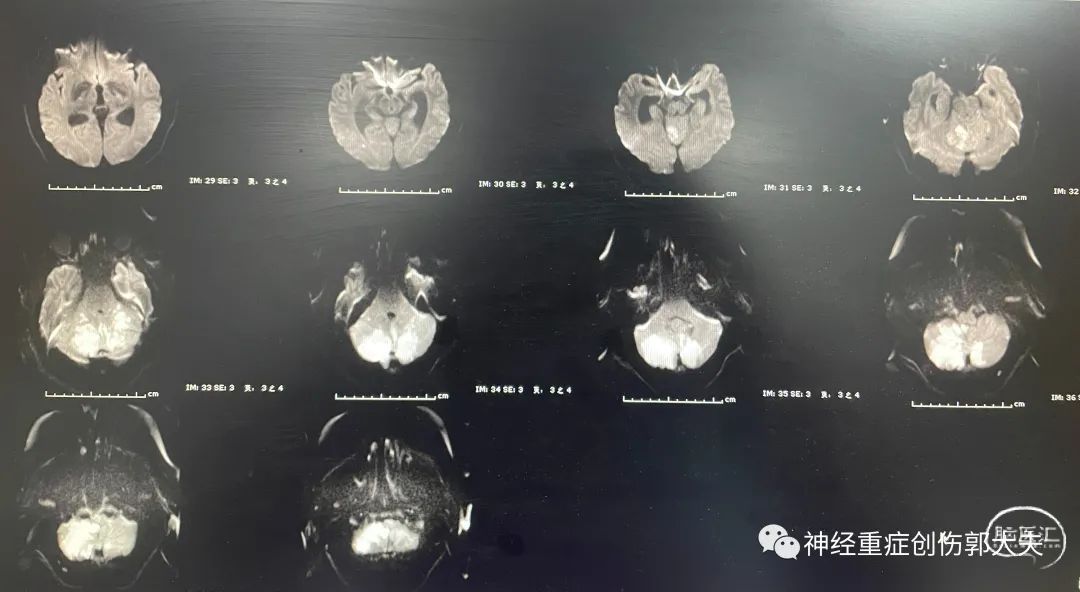

患者女性,34岁,主因“头晕4天,加重2天”入住我院神经内科,神志清楚,完善头颅核磁显示双侧小脑半球及丘脑大面积脑梗死。

通过与患者家属详细交流后先行侧脑室外引流,如病情加重,再行后颅窝减压术。术后复查移动CT显示引流管位于侧脑室内。